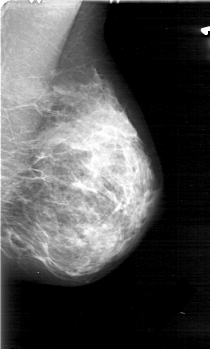

D_4031_1.LEFT_CC

FILE: D_4031_1.LEFT_CC.OVERLAY

TOTAL_ABNORMALITIES 1

ABNORMALITY 1

LESION_TYPE MASS SHAPE OVAL MARGINS OBSCURED

ASSESSMENT 0

SUBTLETY 5

PATHOLOGY BENIGN

TOTAL_OUTLINES 1

BOUNDARY